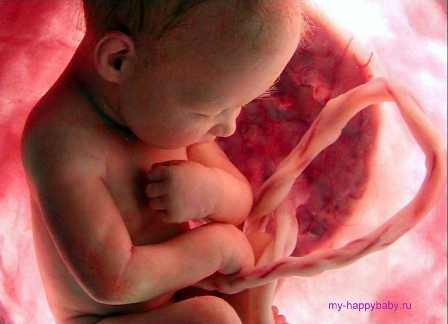

На тридцатой неделе беременности плод продолжает расти, что вызывает увеличение окружности живота. В 30 недель беременности растущий плод выглядит практически как новорождённый. Отличие заключается в размерах. В большинстве случаев ребёнок располагается головкой вниз. Это необходимое положение для рождения.

На тридцатой неделе беременности кожа ребёнка приобретает розовый оттенок. Длительное время кожа отличалась тонкостью и ярко-красным цветом. Несколько недель назад образовалась подкожная жировая клетчатка. Доля подкожного слоя в тридцать недель беременности увеличивается на 6% от общей массы тела. Именно поэтому кожа приобретает прочность, а складки постепенно разглаживаются. Кровеносные сосуды не просвечивают через дерму и эпидермис.

Плод размещается в матке более компактно из-за своих значительных размеров. Отмечается сгибательная поза, при которой ножки поджаты к животику, а ручки – к грудной клетке. Подбородок плода приведён к груди. Данная поза является наиболее удобной для плода, которому в матке уже недостаточно места в тридцать недель беременности.

Тело плода становится более пропорциональным. Животик, ножки и ручки, щёчки становятся более пухлыми. Ребёнок может строить гримасы, улыбаться, зевать, сжимать кулачки и сосать пальчики. Стопы плода могут выглядеть крупными из-за подкожного жира.